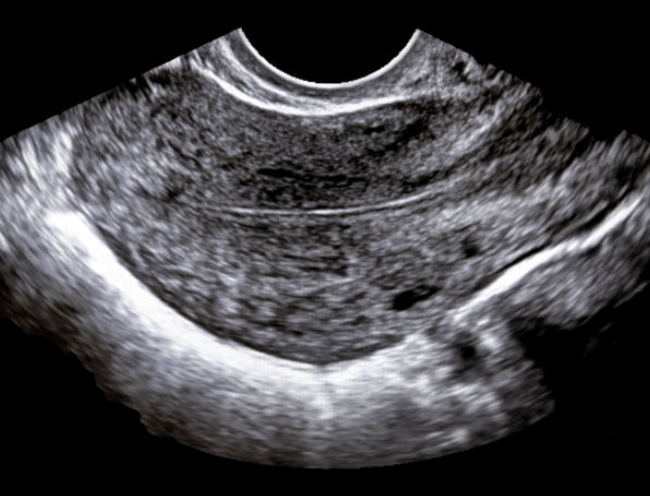

Mi tolgo le mutande, mi stendo sul lettino, prepara gli strumenti e dice: “Metto a monitor”. Silenzio.

La Dottoressa fa una faccia strana, silenzio, sembra perplessa.

D: “Non so. È una situazione molto strana quella che vedo. Questa potrebbe essere una camera, oppure un polipo grande quanto l’utero”.

D: “Io spero per lei che sia una camera. Si faccia un altro test di gravidanza”